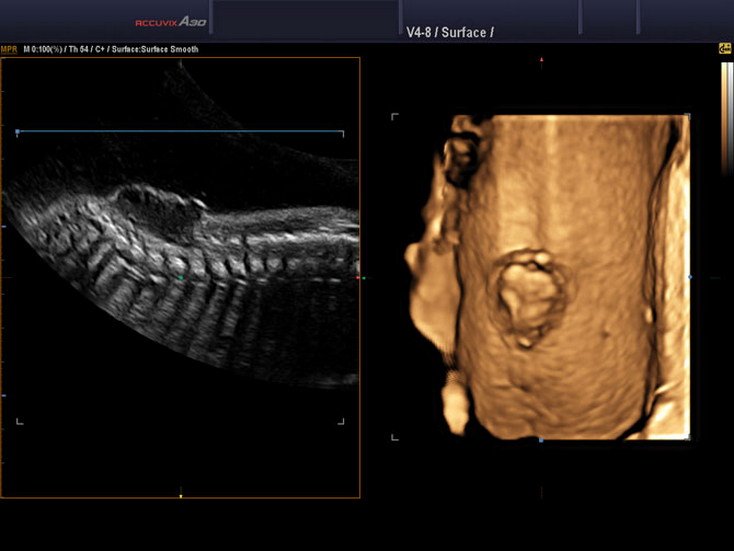

Spinal Defect Sonography